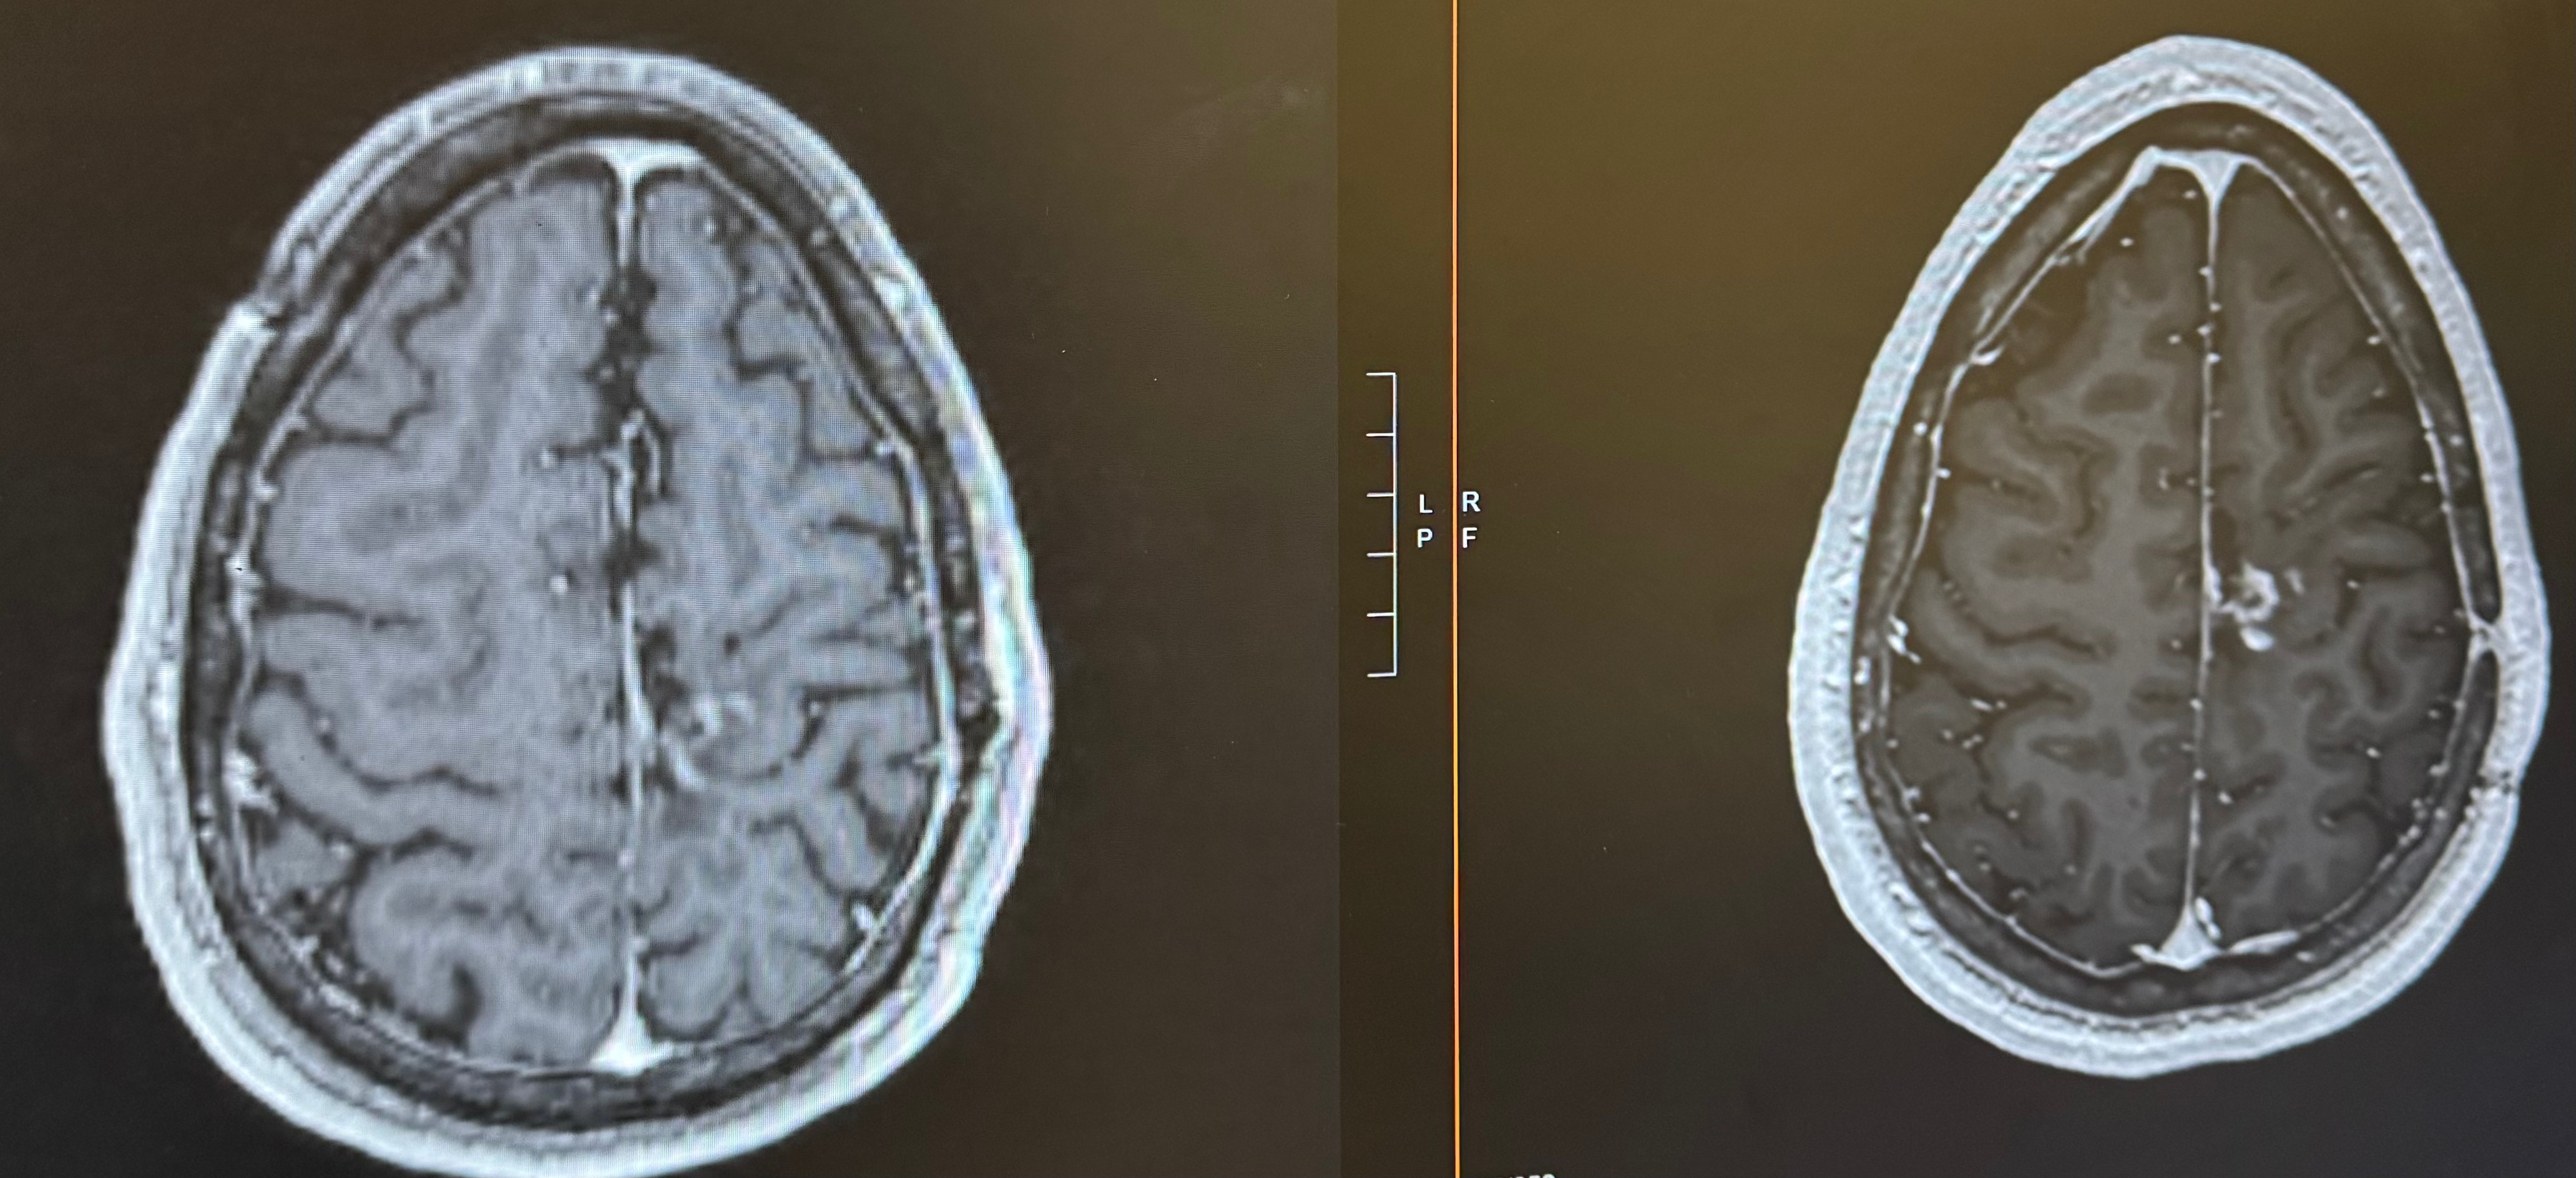

(right side is an older scan, left side is a recent scan. The white area just to the right of the midline is the tumor)

It was truly hard to believe. In the past, I would be immediately hesitant to fully accept the good news because experience has conditioned me to expect the other shoe to drop. However, one of the many things my partner, Chris, has taught me is to lean into the good news. So, I celebrated!

The next scan showed slightly further decrease in size, and my most recent scan showed stability if not further decrease. I have my next scan this Tuesday (March 17th), which I hope continues the good news. Leading up to the MRIs, I will always get scanxiety about when this ends up being too good to be true, but in between those scans I continue planning to live life fully.